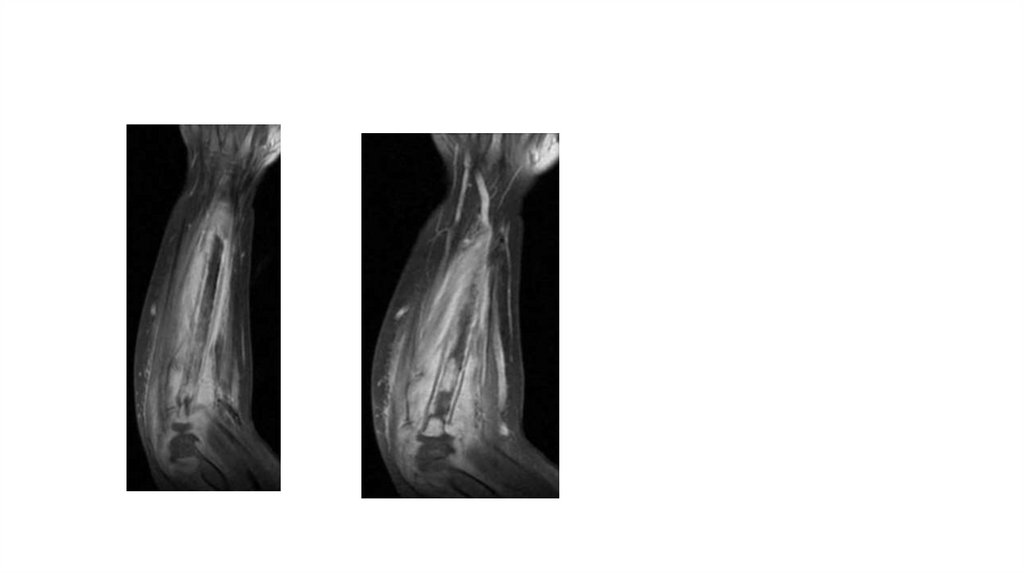

Воспалительные заболевания опорнодвигательного аппарата

«Воспалительные

заболевания опорнодвигательного аппарата»